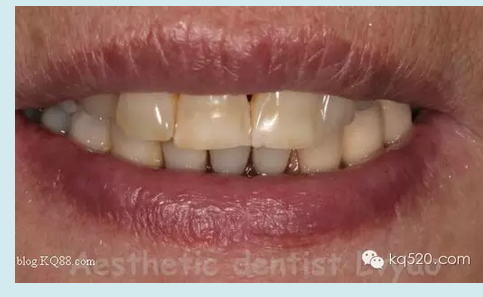

修復(fù)后口外影像